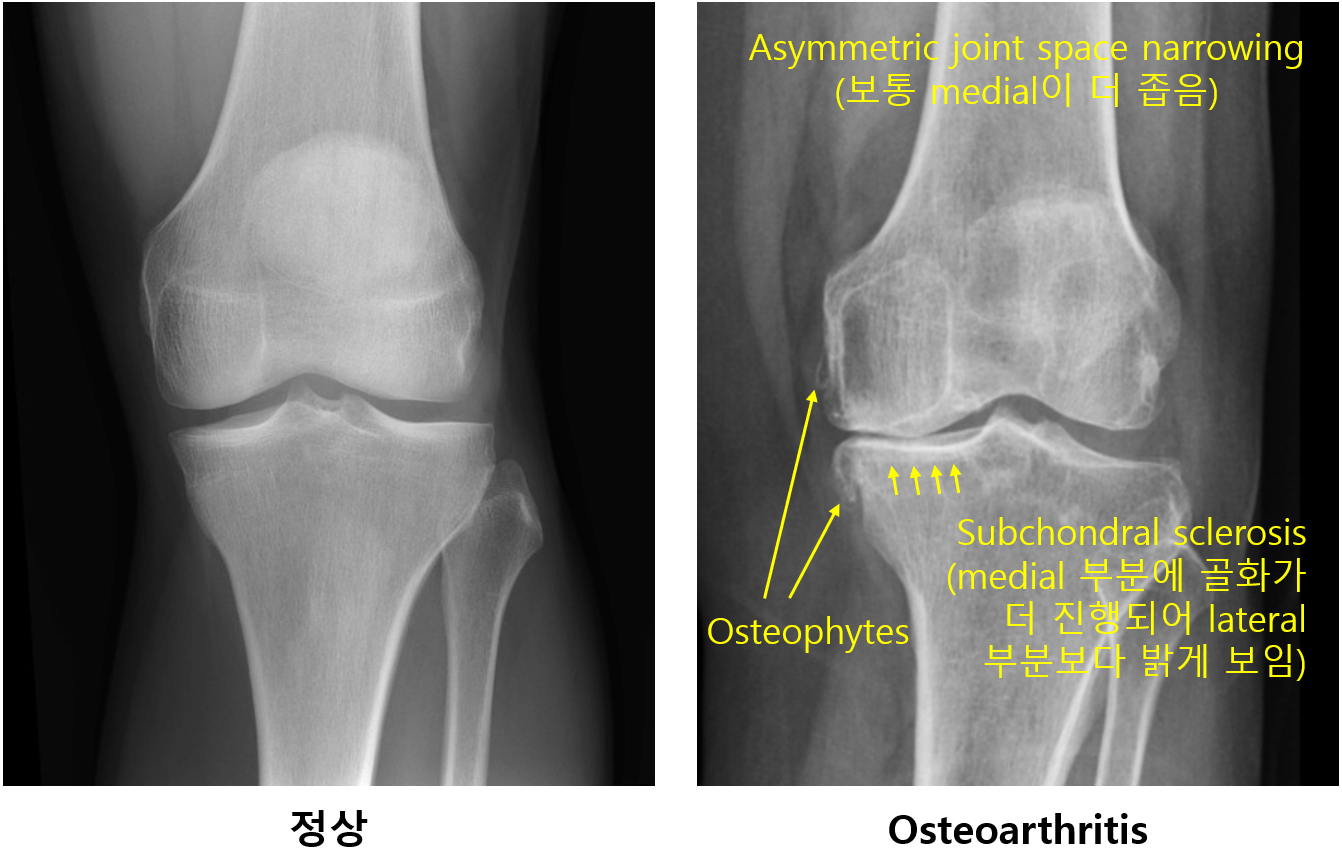

2) Plain X-ray

(1) Asymmetric joint space narrowing

(2) Osteophytes

(3) Subchondral bone sclerosis, subchondral cyst